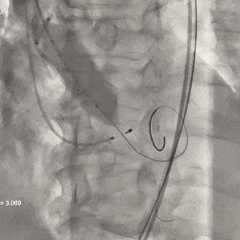

左冠提前预埋冠脉导丝

导丝顺利跨瓣